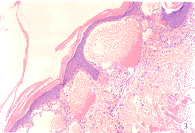

5.瀰漫性軀體血管角化瘤 真皮乳頭層血管擴張,形成襯有內皮細胞並充滿血液的腔隙,其周圍由角化亢進和棘層肥厚的表皮包繞電鏡下內皮細胞周細胞和成纖維細胞內見有特徵性的電子緻密小體。